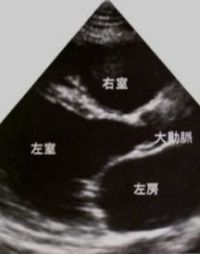

<心エコー>

左室拡大の所見が見られます。

拡張型心筋症(心エコー) (第96回医師国家試験C7問題)